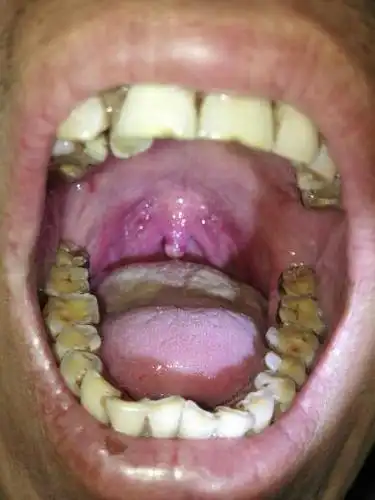

医生在电子喉镜下所见:喉部粘膜慢性充血,悬雍垂见淡红色乳头状新生物

悬雍垂乳头状瘤?